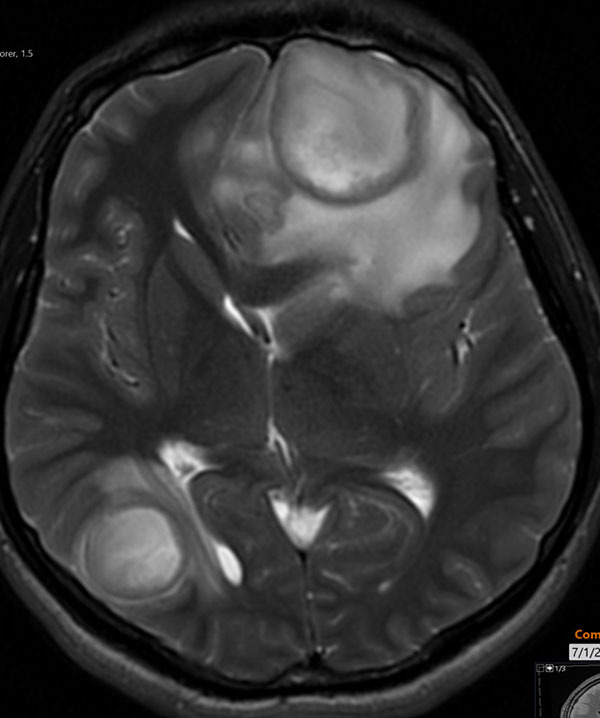

Symptoms typically have an indolent onset, starting with low fevers and headache, and progressing to vomiting and neurologic changes. A head CT or magnetic resonance imaging (MRI) of the brain allows for an accurate diagnosis. See Figures 9 A-B for a brain MRI that depicts the typical findings of abscesses secondary to Streptococcus. Figures 10 A-C show a classic epidural abscess. Given the possibility of elevated intracranial pressure, lumbar puncture should be avoided because of the risk of herniation.

Figure 9B. Brain Magnetic Resonance Imaging with Fluid and Edema |

![]() |

Brain magnetic resonance imaging T2 showing complex fluid within the lesion and extensive adjacent edemas Used with permission from Sean Kelleher, MD, Dayton Children’s Hospital. |